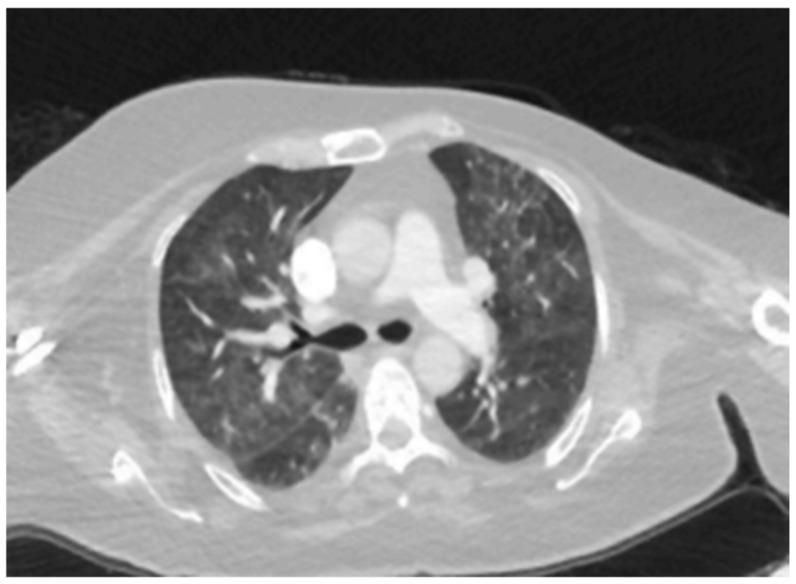

CDK4/6 inhibitors (CDK4/6i) have revolutionized the treatment of hormone receptor-positive HER2 negative (HR(+)/HER2(-)) breast cancer. Despite their efficacy, interstitial lung disease (ILD) remains a rare but potentially fatal adverse effect. This study aims to evaluate the incidence and clinical characteristics of ILD associated with CDK4/6 inhibitors in breast cancer patients in Turkey. : A retrospective multicenter analysis included 464 breast cancer patients treated with CDK4/6 inhibitors between January 2017 and April 2024. Patients receiving ribociclib or palbociclib were evaluated for the development of ILD. Radiological assessments were performed to confirm ILD and exclude other conditions. Clinical characteristics, treatment regimens, and outcomes were analyzed. : ILD was identified in 10 patients (2.1%). The average age of the affected patients was 62.5 ± 9.85 years. Hypersensitivity pneumonitis and nonspecific interstitial pneumonia (NSIP) were the most common radiological patterns. Palbociclib was implicated in six cases, while ribociclib was associated with four cases. Grade 3 pulmonary toxicity was observed in eight patients, and Grade 4 toxicity in two patients. One patient who was on palbociclib died due to ILD. No significant correlation was found between ILD and age, smoking status, lung metastases, or prior thoracic radiotherapy. : The incidence of CDK4/6 inhibitor-associated ILD in Turkish breast cancer patients appears higher than previously reported in clinical trials. More robust, long-term studies are necessary to identify potential risk factors and mitigate ILD-related mortality.

细胞周期蛋白依赖性激酶4/6抑制剂(CDK4/6i)彻底改变了激素受体阳性、人表皮生长因子受体2阴性(HR(+)/HER2(-))乳腺癌的治疗方式。尽管其疗效显著,但间质性肺疾病(ILD)仍然是一种罕见但可能致命的不良反应。本研究旨在评估土耳其乳腺癌患者中与CDK4/6抑制剂相关的ILD的发生率和临床特征。:一项回顾性多中心分析纳入了2017年1月至2024年4月期间接受CDK4/6抑制剂治疗的464例乳腺癌患者。对接受瑞博西尼或哌柏西利治疗的患者进行ILD发生情况评估。进行影像学评估以确诊ILD并排除其他疾病。分析临床特征、治疗方案和结局。:10例患者(2.1%)被确诊为ILD。受影响患者的平均年龄为62.5±9.85岁。过敏性肺炎和非特异性间质性肺炎(NSIP)是最常见的影像学表现。哌柏西利涉及6例,而瑞博西尼与4例相关。8例患者出现3级肺部毒性,2例患者出现4级毒性。1例接受哌柏西利治疗的患者因ILD死亡。未发现ILD与年龄、吸烟状况、肺转移或既往胸部放疗之间存在显著相关性。:土耳其乳腺癌患者中与CDK4/6抑制剂相关的ILD发生率似乎高于先前临床试验报告的发生率。需要更有力的长期研究来确定潜在风险因素并降低与ILD相关的死亡率。